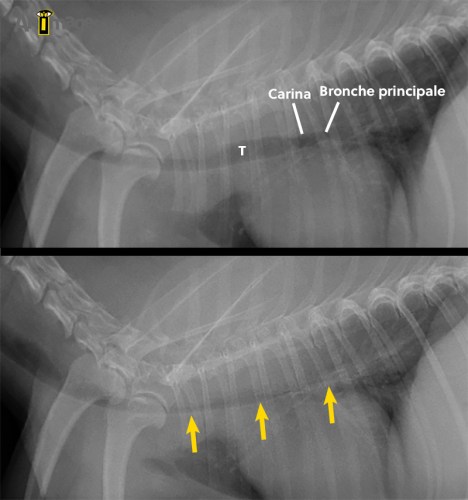

L’examen fluoroscopique effectué après palpation trachéale pour induire de la toux montre hors de tout doute un collapsus sévère affectant non seulement la trachée, mais aussi les bronches principales. L’implication des bronches est importante car elle limite la pose d’une prothèse endoluminale (stent), celui-ci ne pouvant être placé que dans la trachée et jusqu’à environ 1 cm de la carina.

Ces images proviennent de deux instants de la boucle fluoroscopique, illustrant la variation de diamètre important qui a lieu durant la toux chez ce petit chien. Notez le collapsus complete de la trachée (T) thoracique, de la carina et des bronches principales survenant durant cet épisode de toux.